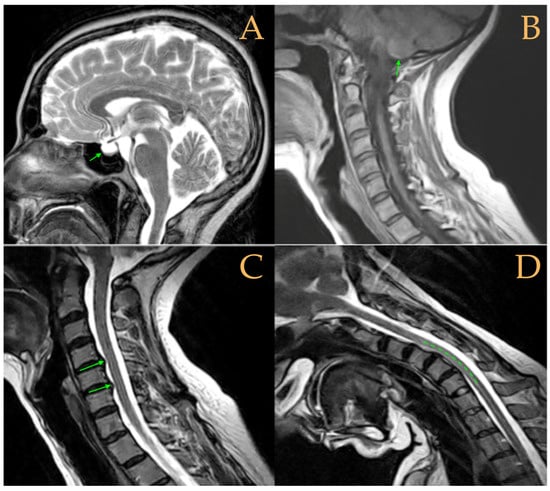

The MRI showed a descent of the cerebellar tonsils, increased supracerebral space, and micro lacunae in the bilateral white matter and the left basal ganglia. Upper cervical kyphosis and straightening in the lower levels. Surgical arthrodesis at C4-C5 and C5-C6. Cervical, thoracic and lumbar protrusions. Ischemia and oedema in the cervical and thoracic spinal cord. Slight cervical rotoscoliosis. Disc protrusions: T7-8, T11-L1, L2-L3-L4, and disc herniation L4-L5. Loss of the lumbar lordosis. Conus medullaris at the level of the middle third of the L1 vertebra (Figure 2). The X-ray images of the entire spine showed levoconvex thoracolumbar scoliosis of 21°, dysmetria of the lower extremities with shortening of the right lower extremity by 10 mm, with respect to the level of the hip, and 99 mm at the level of the iliac crests, 16° cervical lordosis, 49° thoracic kyphosis, and 59° lumbar lordosis.

Figure 3. Imaging of patient 3. A: Empty sella turcica (arrow); B: discrete descent of the cerebellar tonsils (arrow); C: C4C5 and C5C6 disc protrusions (arrows); and D: tense spinal cord in cervical flexion (interrupted line).